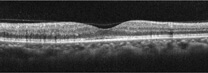

正常な網膜

目の表面から入ってきた光は角膜・水晶体・硝子体を通過して網膜に到達します。

網膜で得られた情報は、視神経を介して脳に伝達されます。

網膜の断層像では、黄斑が凹んでいることがわかります。